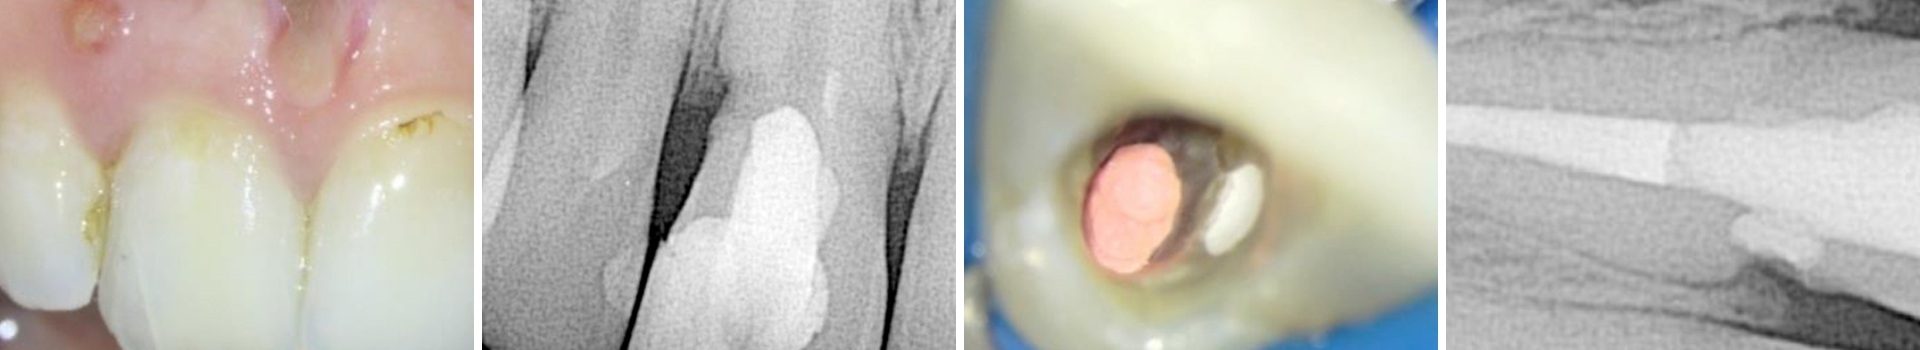

Abbildung 2

Zu sehen ist der blutende Defekt im zervikalen Bereich zu Beginn der Wiedereröffnung des Wurzelkanals.

Zu Beginn der Behandlung wurde zunächst so viel vom Gutta-Percha wie nur möglich entfernt und der Wurzelkanal anschließend desinfiziert. Man konnte eine Blutung des resorptiven Defekts erkennen. Der Kanal und der Defekt wurden mit Kalziumhydroxid gefüllt und der Zugang mit IRM versiegelt (Abb. 2).

Nach zwei Wochen stellte sich die Patientin symptomfrei vor. Die Fistelöffnung war verschwunden und der resorptive Defekt blutete nicht mehr. Die Behandlung wurde fortgesetzt und erneut wurde Kalziumhydroxid in den Wurzelkanal gefüllt. Da der resorptive Defekt trocken und zugänglich war,wurde entschieden den resorptiven Defekt mit BC Putty durch die Zahneröffnung (internes Vorgehen) zu füllen (Abb. 3).